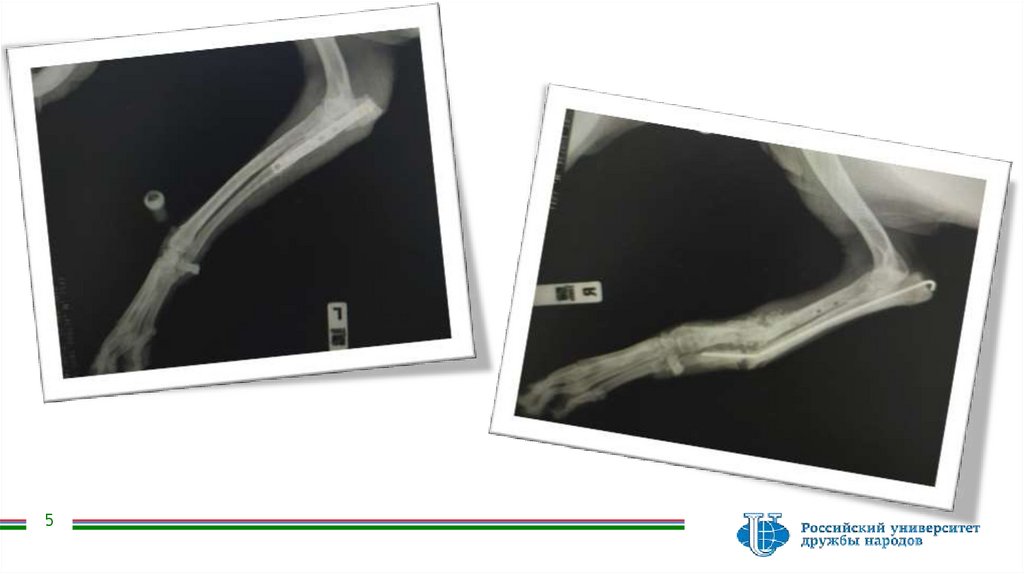

Назначенная рентгенография показала следующее

4

5.

5